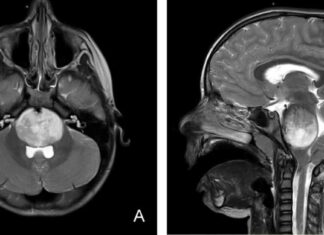

CAR-T Therapy Shows Promise in Treating Aggressive Brain Tumors in Young Patients

Michelle Monje-Deisseroth, a medical student about 20 years ago, treated patients with a type of brain tumor called diffuse intrinsic pontine gliomas, or DIPG. These tumors are difficult to treat because they wrap around...